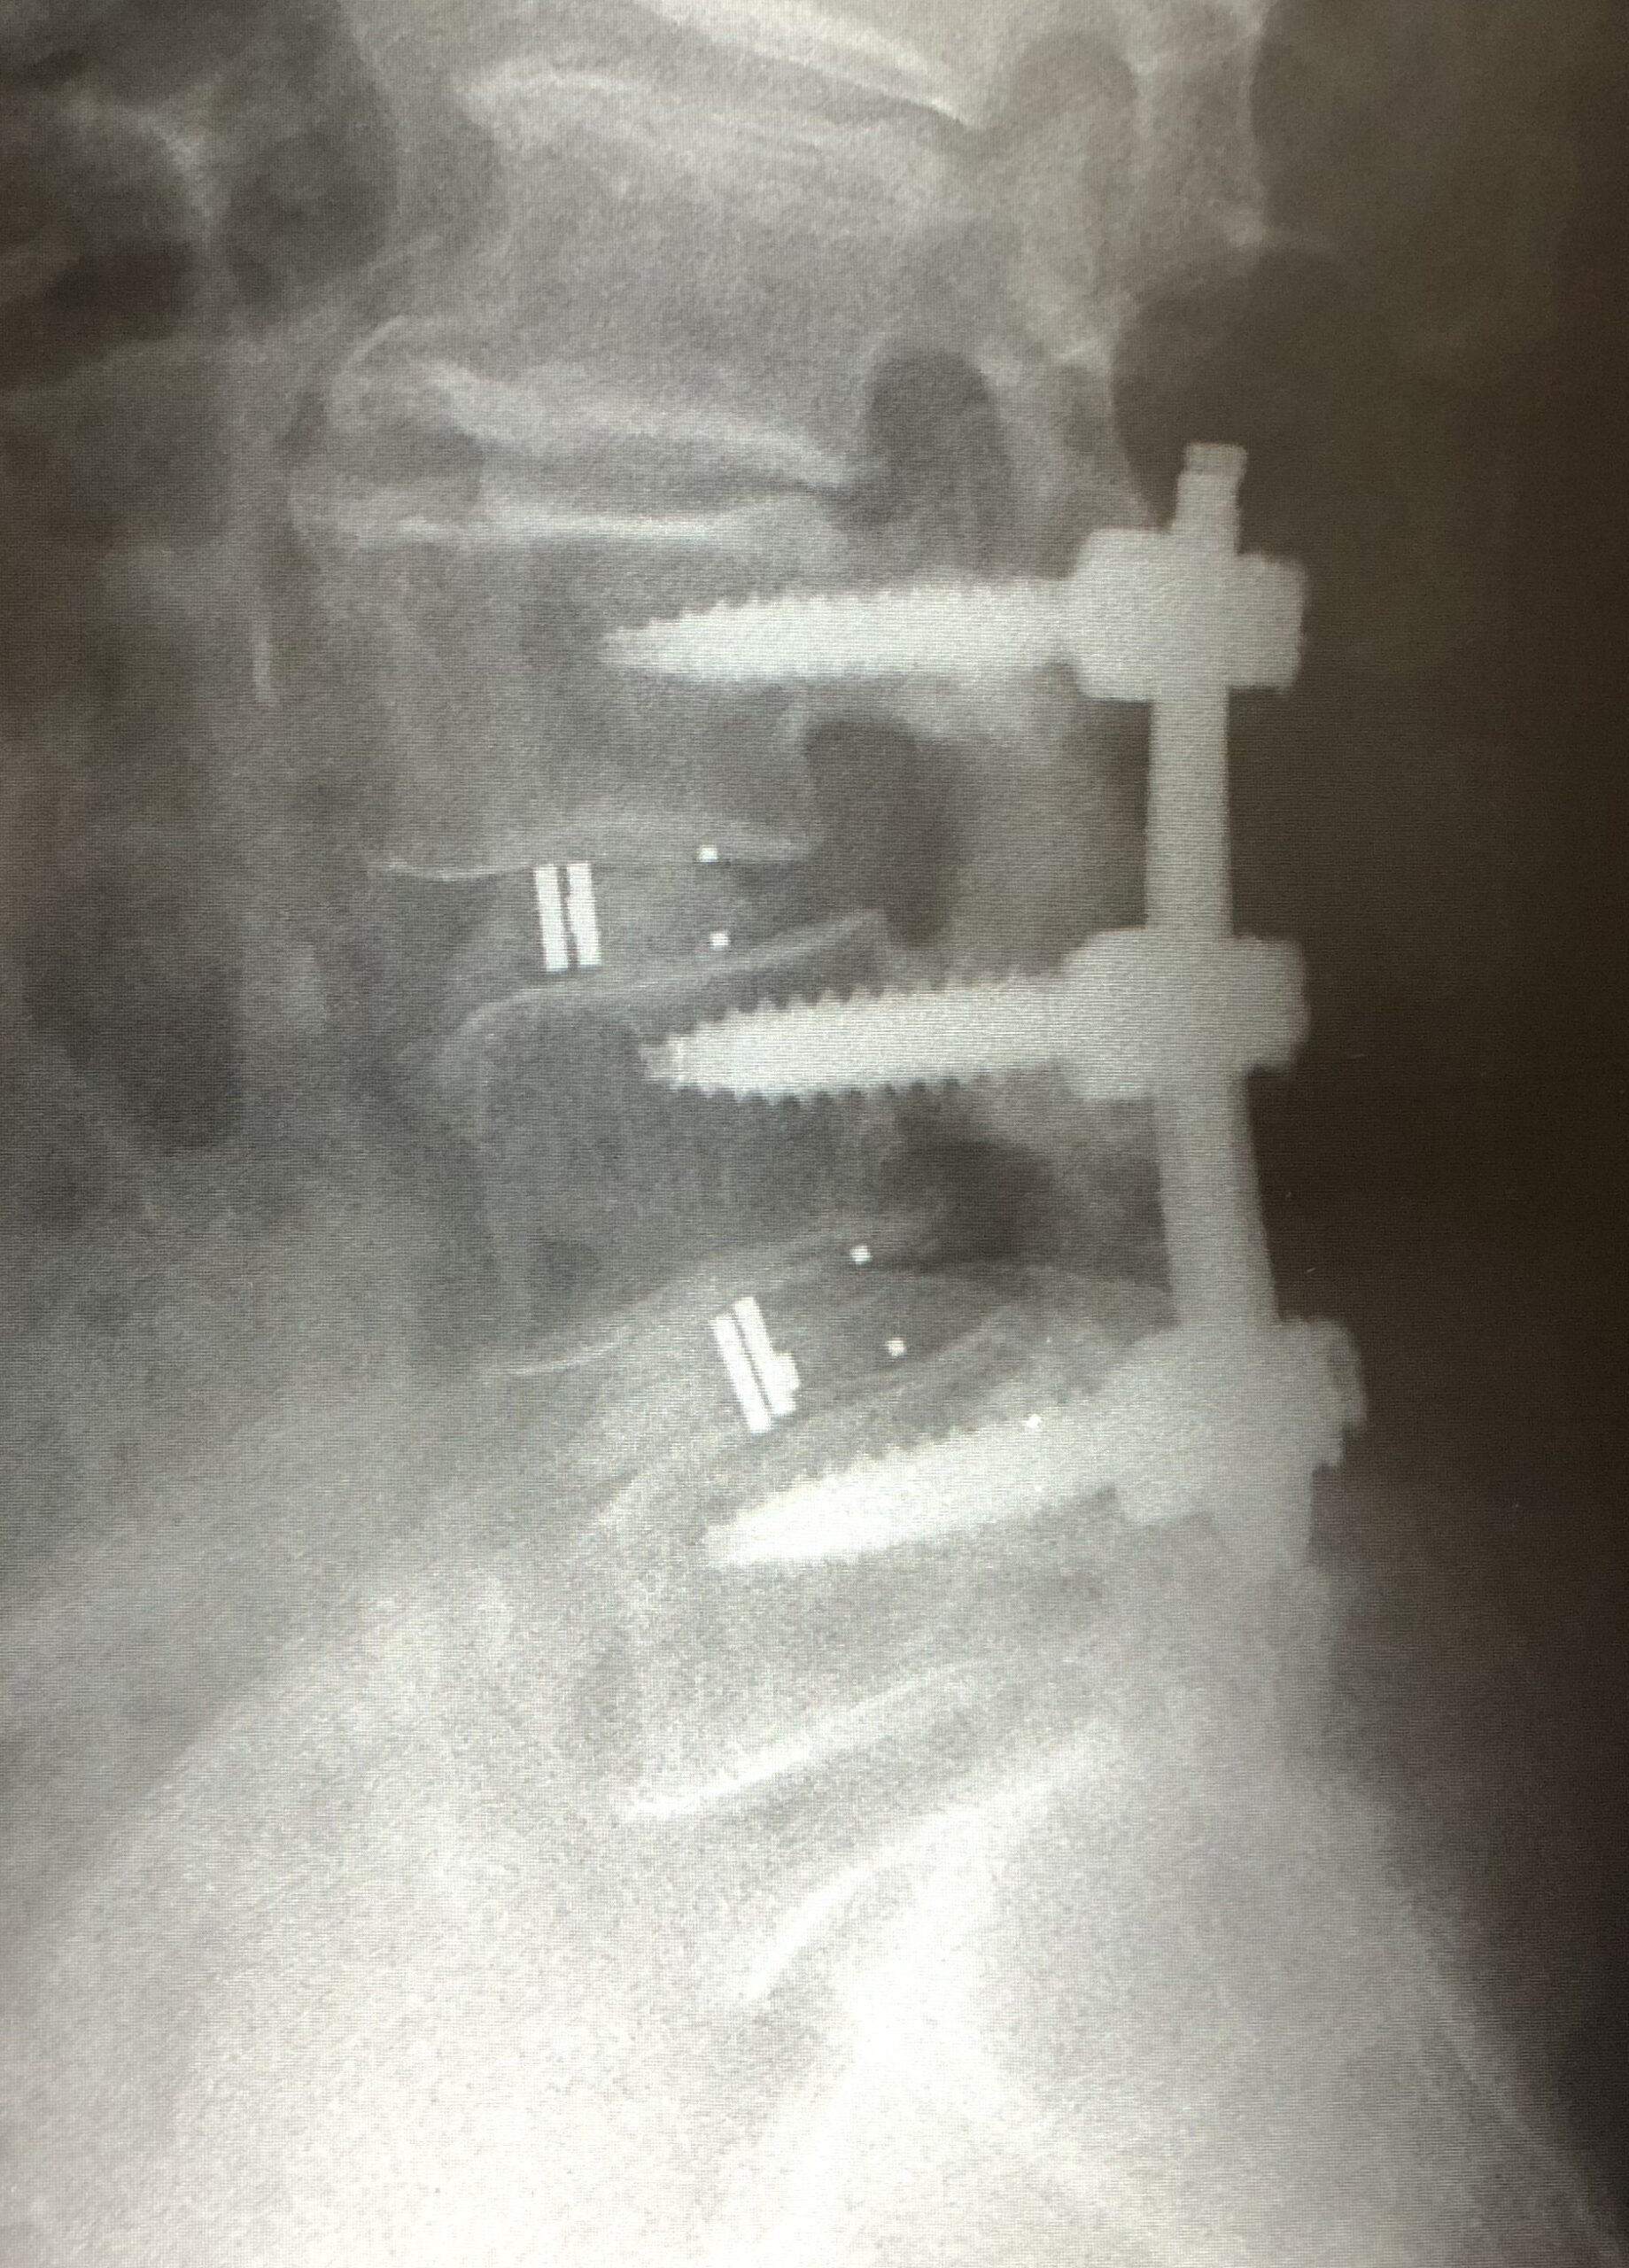

脊椎のすべりにより高度の脊柱管狭窄がある場合に、後方からすべりの矯正や神経の除圧が同時に行える手術です。

| 術前 | 術後 | |

| X線 |